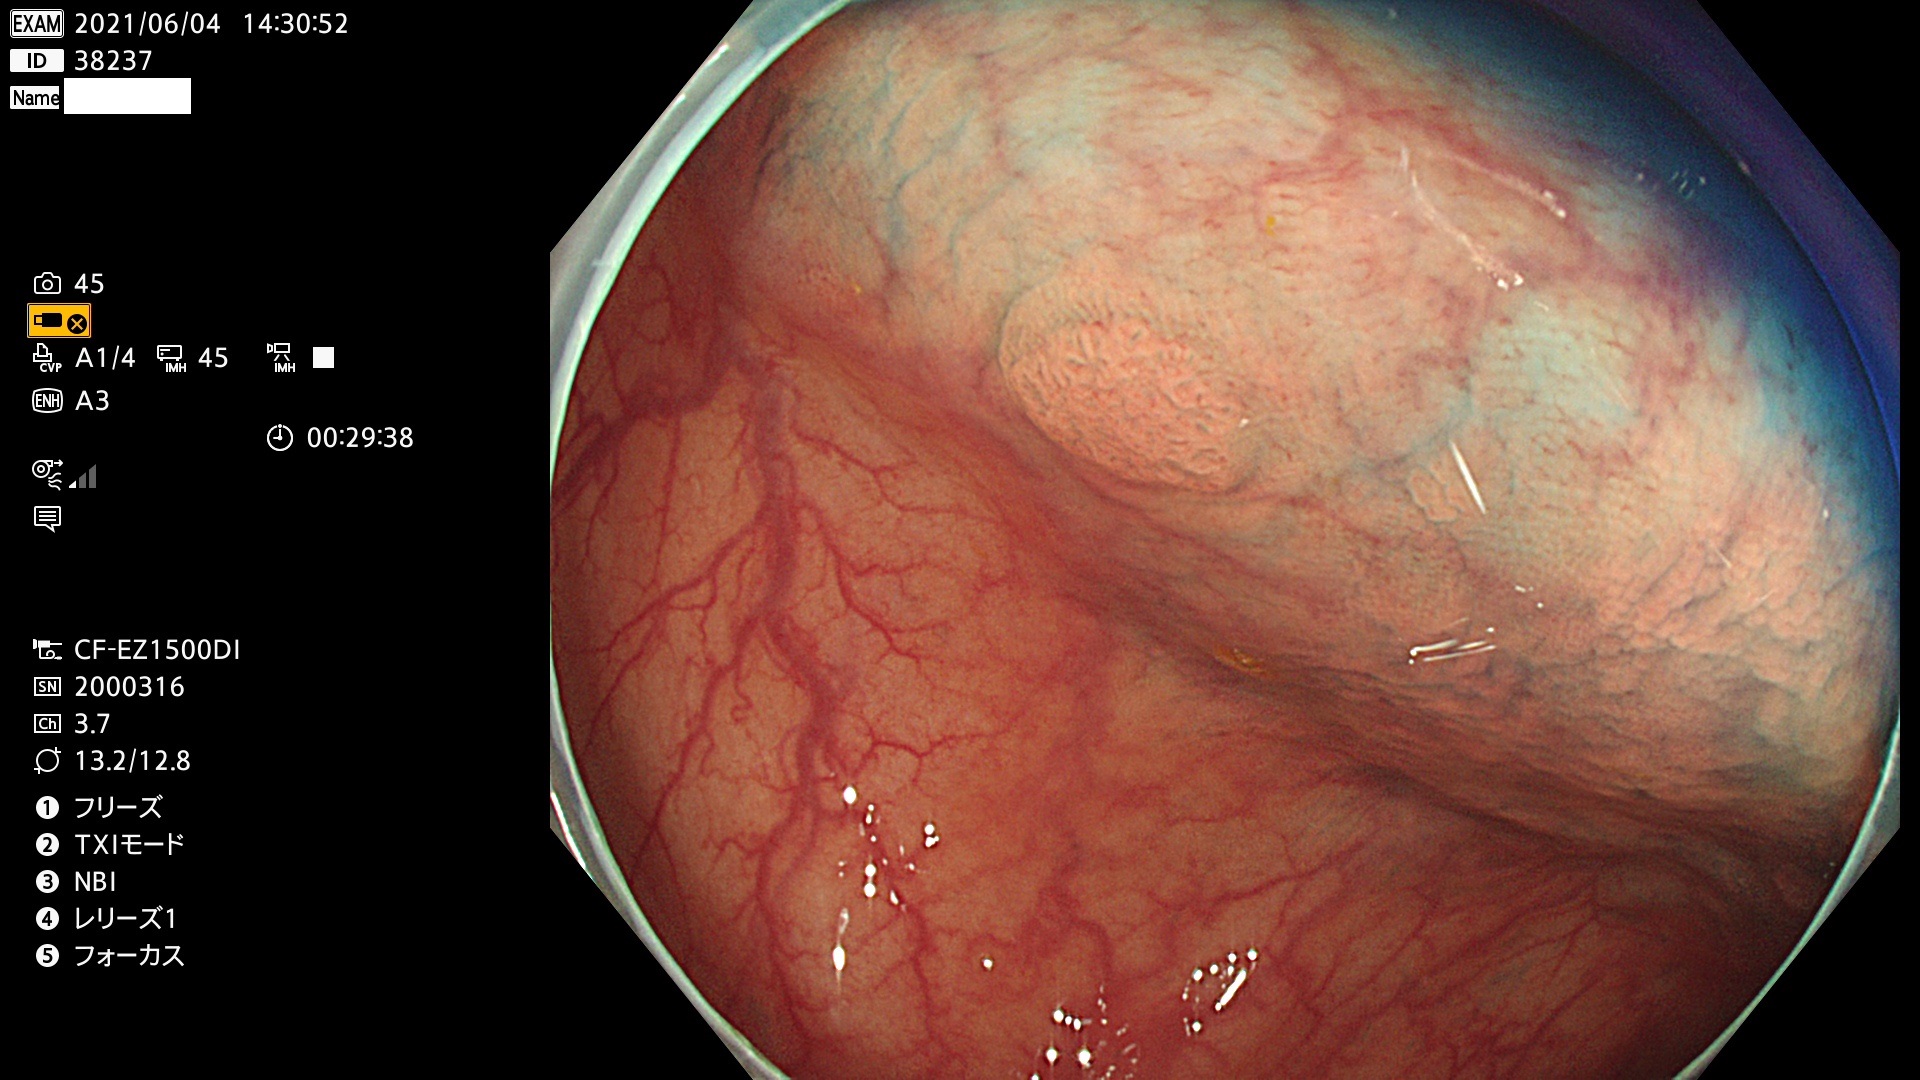

38200 38201 38202 38203 38204 38208 38209 38210 38211 38212 38213 38214 38215 38219 38220(SSAPのみ) 38221 38225 38226 38227 38228 38229 38230 38231 38232(SSAPのみ) 38233 38234 38235 38237 38238 38239 38240 38241 38242 38244 38245 38246 38247 38248 38249 38250 38251 38252 38253 38254 38256 38257 38258 38259 38260(SSAPのみ) 38262 38265 38267 38268(SSAPのみ) 38269 38270 38272 38273 38274 38276 38278 38280 38281 38282 38283 38284 38287 38288 38289 38290 38291 38292 38295 38296 38297 38298 38299(SSAPのみ)

発見困難で危険性の高い平坦型病変(上記100名より抽出)